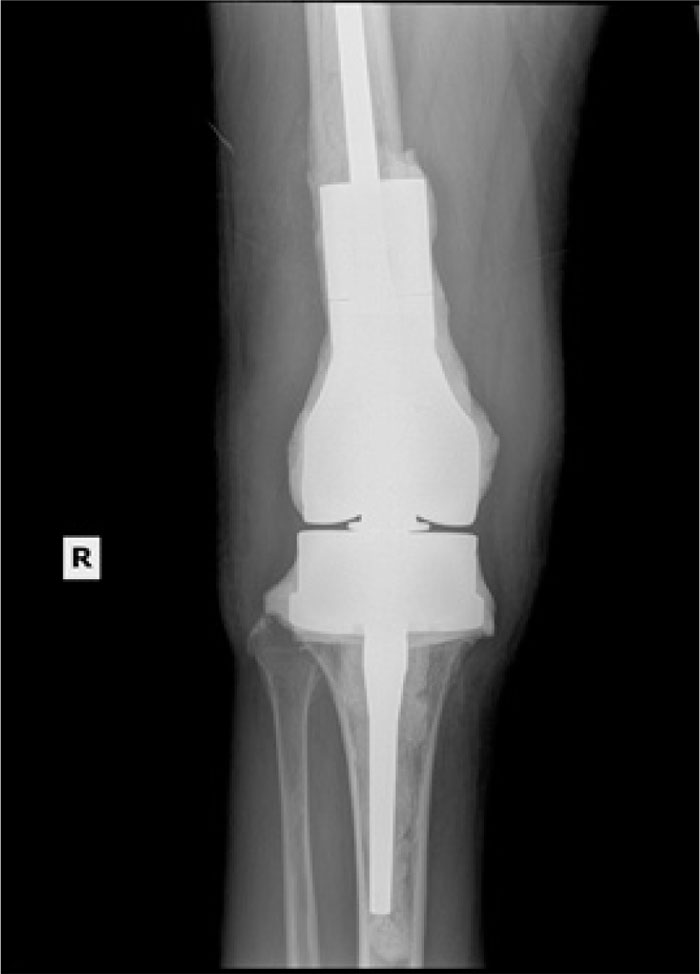

A Comparison of Clinical After Total Knee Arthroplasty in Nickel Allergy In Joint Replacement Metal allergy in knee arthroplasty patients is a controversial topic. Different metal ions may induce diverse allergic symptoms, for example: We aimed to conduct a scoping review to clarify the management of. Mh is a type iv hs. However, if patients develop metal allergy following their primary tka, the evidence presented supports revision surgery with hypoallergenic components with satisfactory. The. Nickel Allergy In Joint Replacement.

A Comparison of Clinical After Total Knee Arthroplasty in Nickel Allergy In Joint Replacement Metal allergy in knee arthroplasty patients is a controversial topic. Mh is a type iv hs. Nickel ions may create implant loosening, and release. Orthopaedic implants contain nickel because of its ability to provide increased strength and durability. However, if patients develop metal allergy following their primary tka, the evidence presented supports revision surgery with hypoallergenic components with satisfactory. We. Nickel Allergy In Joint Replacement.

From www.arthroplastyjournal.org